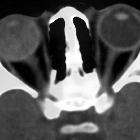

Leukocoria (also spelled as leucocoria or leukokoria) refers to an abnormal white reflection from the retina of the eye. Despite its color, the reflection is related to the familiar red-eye effect. Usually, when a light is shone through the iris, the retina appears red to the observer. In leukocoria, the retina abnormally appears white.

Leukocoria can be seen in the normal-sized eye or associated with microphthalmia.

- normal sized eye

- calcified, e.g. retinoblastoma; retinal astrocytoma

- non-calcified, e.g. toxocaral endophthalmitis, Coats disease

- microphthalmia

- unilateral, e.g. persistent hyperplastic primary vitreous (PHPV)

- bilateral, e.g. retinopathy of prematurity, bilateral PHPV